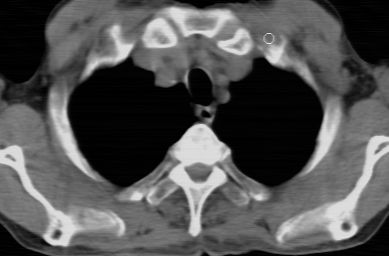

标题: CT24783:m71,既往肺心病史3年,现咳嗽,憋喘。 [打印本页]

标题: CT24783:m71,既往肺心病史3年,现咳嗽,憋喘。

1、左肺上叶spn,毛刺+分叶+血管集束征,考虑周围型肺癌可能性大

2、全小叶性肺气肿。

1)左肺上叶周围型肺癌可能。2)两肺全小叶型肺气肿。

左上周围型肺癌,全小叶型肺气肿。